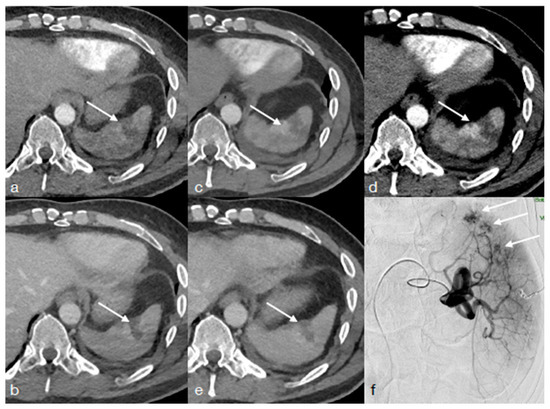

- Iacobellis, F.; Iacobellis, F.; Scaglione, M.; Scaglione, M.; Brillantino, A.; Brillantino, A.; Scuderi, M.G.; Scuderi, M.G.; Giurazza, F.; Giurazza, F.; et al. The additional value of the arterial phase in the CT assessment of liver vascular injuries after high-energy blunt trauma. Emerg. Radiol. 2019, 26, 647–654. [Google Scholar] [CrossRef]

- Uyeda, J.W.; LeBedis, C.A.; Penn, D.R.; Soto, J.A.; Anderson, S.W. Active Hemorrhage and Vascular Injuries in Splenic Trauma: Utility of the Arterial Phase in Multidetector CT. Radiology 2014, 270, 99–106. [Google Scholar] [CrossRef] [PubMed]